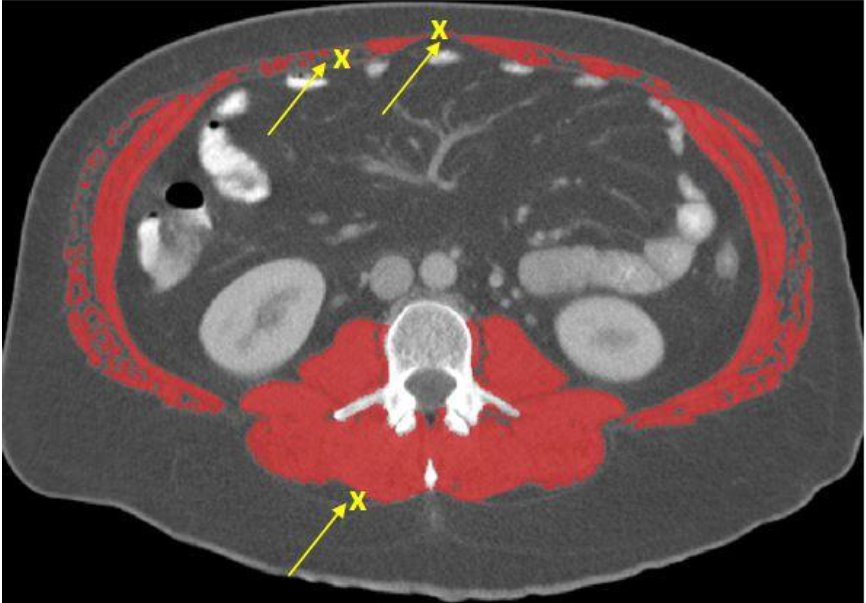

·For skeletal muscle analysis, all muscles at the L3 region will be analyzed (TAG 1- Red, HU Range: -29 to +150)

·Fascia bundles that connect to muscle should not be analyzed as muscle

·Be careful not to include non muscle structures touching the psoas or other muscles

Be careful not to analyze organs that might be touching the skeletal muscle such as intestines, liver, or kidneys as muscle.